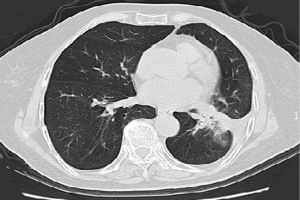

A 47-year-old, non-smoking female was referred to our hospital in January 2018 with a 1-month history of cough and phlegm. A chest computed tomography (CT) scan revealed a 5.0 cm mass in the left lower lung associated with multiple nodules in both lungs (Figure 1). Tumor biopsy pathology conducted on January 31, 2016, revealed that the patient had a stage IV (cT4N3M1) adenocarcinoma. Hematoxylin and eosin (H&E) staining revealed a typical morphology for adenocarcinoma cells (Figure 2).